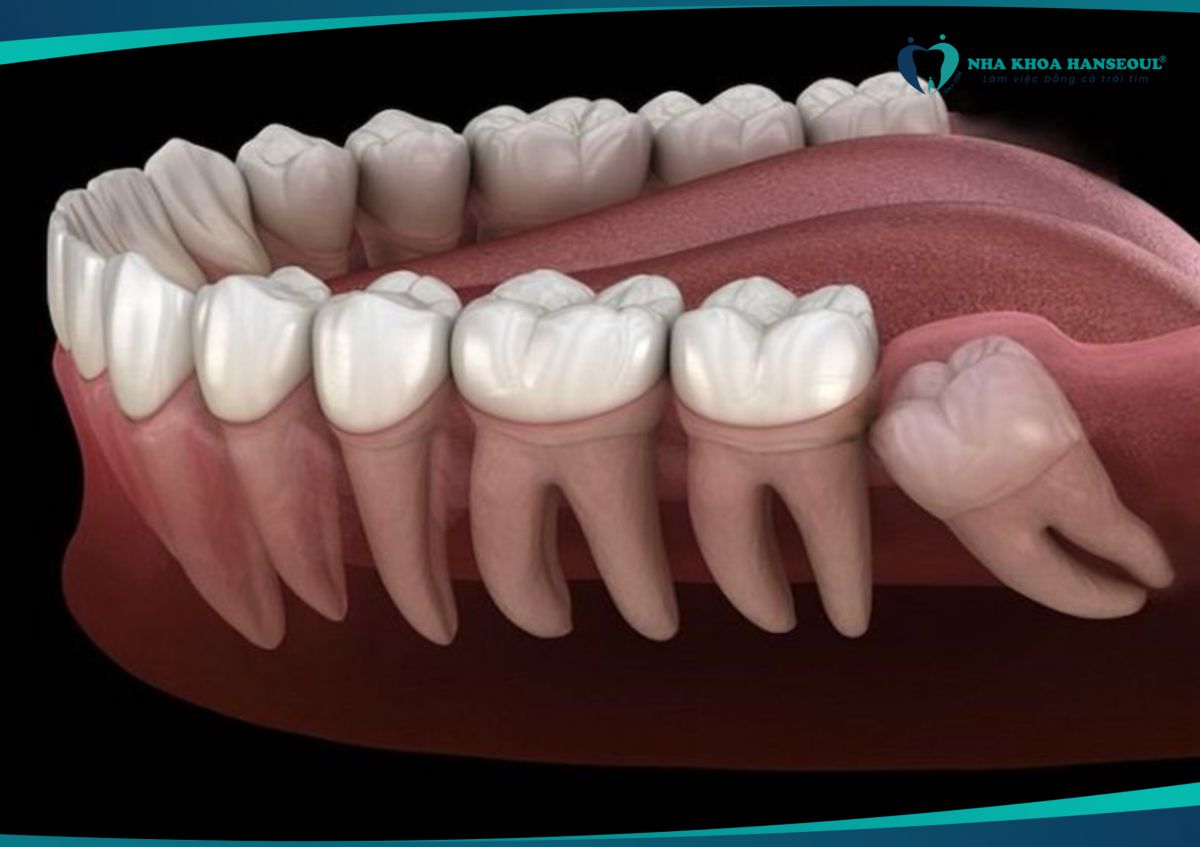

- Dù không đau, răng khôn có thể mọc lệch, đâm vào răng số 7. Điều này dẫn đến tiêu chân răng, xô lệch cả hàm.

- Răng khôn mọc lệch có thể đẩy vào răng số 7, gây sâu răng, lung lay hoặc thậm chí mất răng vĩnh viễn.

7 Gây xô lệch cả hàm răng

- Răng khôn mọc lệch có thể làm thay đổi cấu trúc hàm, khiến các răng khác bị xô lệch, ảnh hưởng đến thẩm mỹ và chức năng nhai.

- Khi không đủ chỗ, răng khôn có thể đẩy vào răng bên cạnh, gây xô lệch.